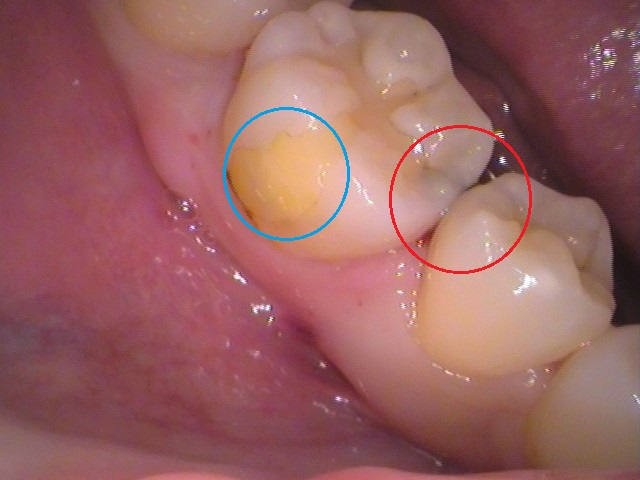

右下の奥歯ですが、

虫歯があるのですが、どこかわかりますでしょうか?

さらに大きくみると

黒くなっている怪しい所がありますね。

どこかというと、

赤丸の箇所にむし歯があります。

ぱっと見ても分かりやすい所です。

青い丸の箇所は、黄色く見えますが、

以前治療をされたレジン(プラスチック樹脂)が入っています。

歯ぐきの際は、なにやら黒くなっていますね。